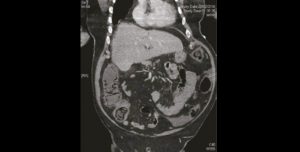

De l’air dans le côlon : quel est votre diagnostic ?

Un patient de 86 ans, relativement autonome, mais résidant en institution, se présente aux urgences à la suite d’une douleur abdominale d’apparition brutale survenue 4 heures avant. Cliniquement, la douleur…